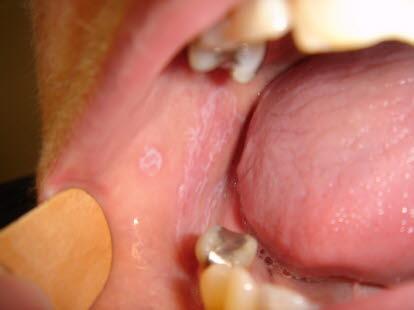

Slimhinneforandringene i munnhulen kan ha litt ulike utseender. Det kan være som et mønster av tråder og nett (retikulær form), det kan være partier som kun er røde (erytematøs form), eller det kan være sårdannelser (erosiv form). Den retikulære formen er lettest å se, den gir ofte lite plager, men den kan være sjenerende når den finnes på tungen. Den erosive formen er den mest plagsomme.

Tilstanden utvikler seg ofte langsomt, og den kan lenge være uten symptomer. Det kan for eksempel være tannlegen som oppdager forandringene i slimhinnen. Forandringene kan være hvite striper, flak eller små knuter. De finnes mest typisk på den delen av munnslimhinnen som vender inn mot tennene, ofte på begge sider i munnen. Slimhinneforandringene kan også forekomme (med avtakende hyppighet) på tungen, i tannkjøttet, på leppene, i munngulvet og i ganen. Over tid vil cirka to av tre få plager med svie og brenning i munnen. Plagene forverres gjerne når de spiser sterkt krydret mat.